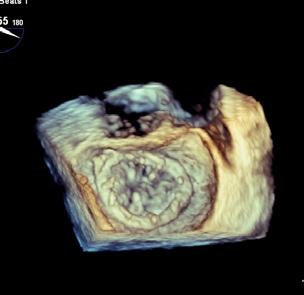

Cazuri disperate în chirurgia cardiacă –atunci când abordul minim invaziv este soluția

Dr. Ion Iovu, Prof. Univ. Dr. Lucian Dorobanțu, Dr. Andreea Bogdan, Dr. Ioana Băjenaru, Dr. Oana Ioniță, Dr. Mădălina Cojocaru, Dr. Toma Iosifescu, Conf. Dr. Cătălin Badiu, Dr. Alexandru Vasilescu